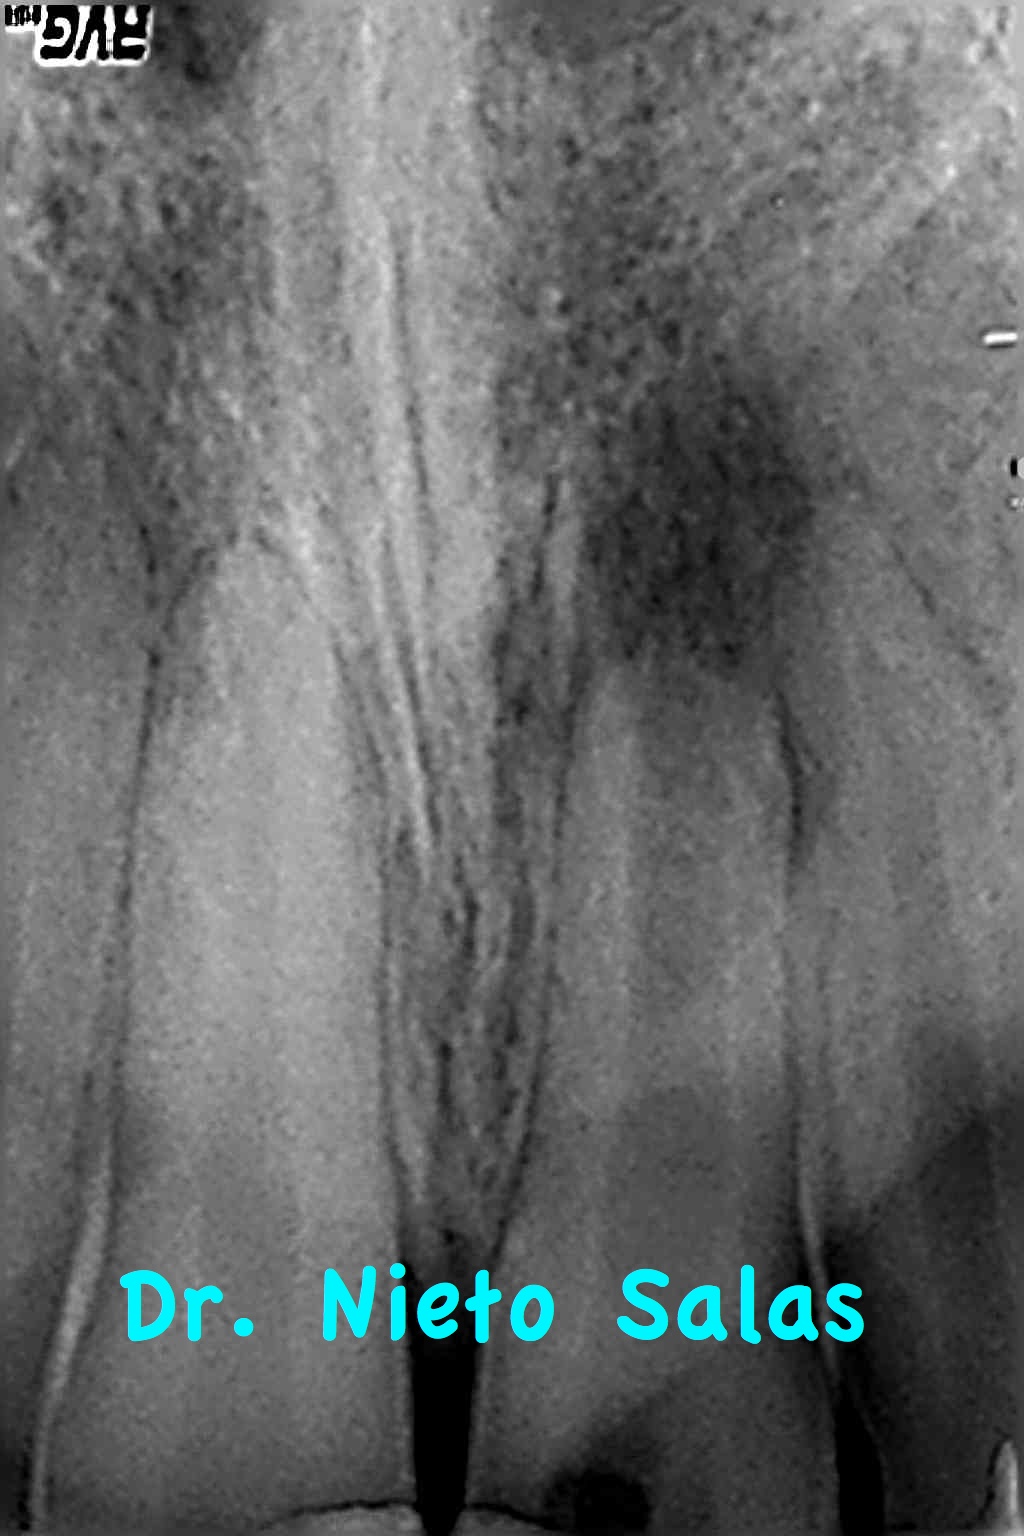

Acude a nuestra consulta un chico que tuvo un traumatismo hace años y que recientemente le ha salido una fístula.

le hacemos una Rx y vemos que se trata de un diente con ápices abiertos: